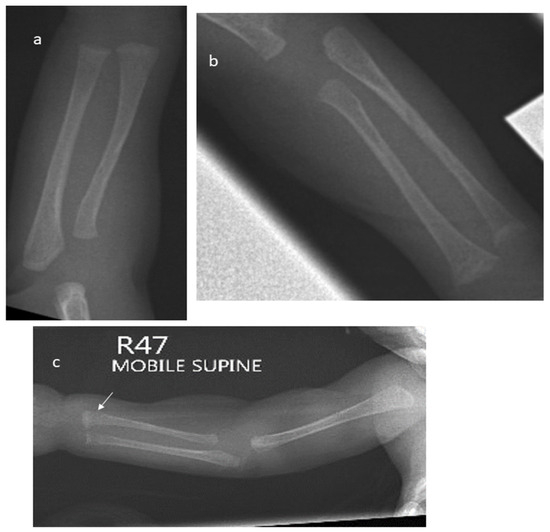

The plain radiographs of all enrolled infants were reviewed by an independent paediatric radiologist who was blinded to the clinical details and biochemical test results. MBDP was identified and graded according to Koo et al. [19] as follows:

- No MBDP: normal density with white line at metaphyseal region

- Grade 1: loss of dense white line at metaphyses and thinning of cortex (Figure 1a)

Figure 1. (a) X-ray of the right forearm in a 6-week-old infant born at 26 weeks showing changes of Grade 1 MBDP. (b) Wrist X-ray of an 8-week-old female infant born at 25 weeks showing cupping and fraying of metaphyses, Grade 2 MBDP. (c) X-ray of the right forearm in an 8-week-old infant born at 24 weeks showing a fracture at the distal end of the radius (marked by arrow). - Grade 2: changes of grade 1 plus irregularity and fraying of metaphyses, with splaying and cupping (Figure 1b)

- Grade 3: bone changes seen in grade 1 and grade 2 in addition to fracture (Figure 1c)